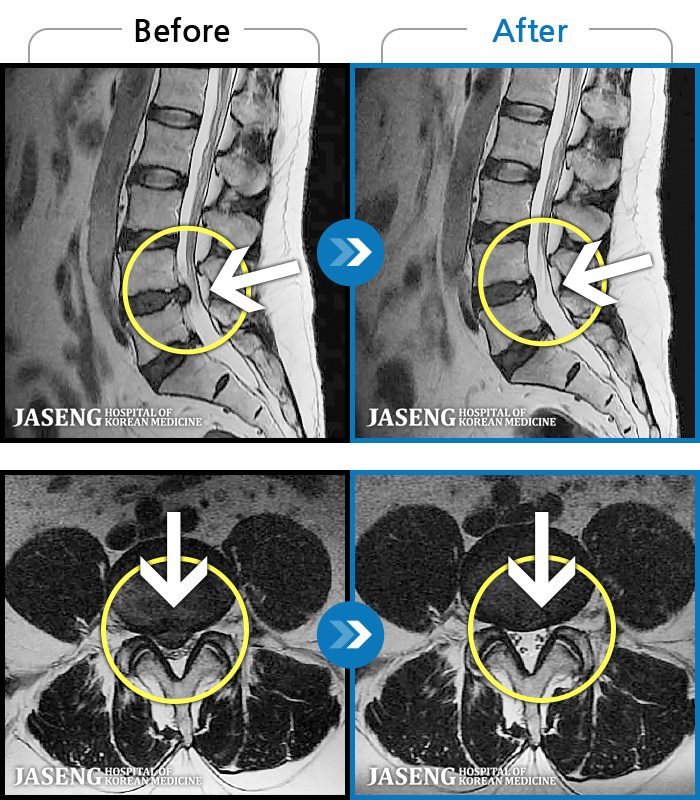

123 MRI ũ ʸ Ȯϼ.

[뱸] 19.11.28~25.05.06